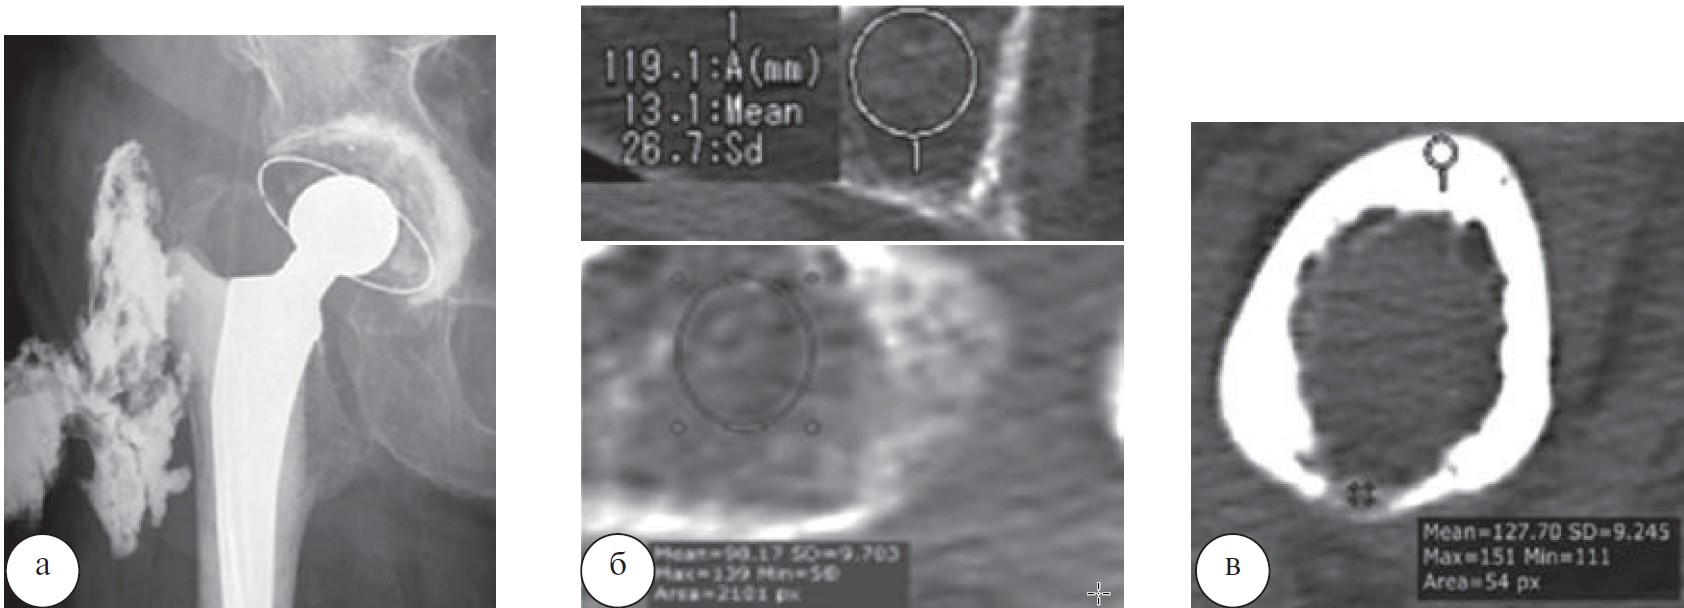

При наличии подострой формы хронического остеомиелита после ревизионного эндопротезирования правого тазобедренного сустава на фистулограммах у 17 больных определялись затеки контрастного вещества в мягкие ткани по наружной поверхности бедра. На аксиальных срезах тазобедренного сустава, после удаления эндопротеза, плотность крыши вертлужной впадины, области малого вертела значительно снижена, корковая пластинка имела неравномерную толщину и плотность. В области малого вертела плотность кости составляла 98,17±9,70 HU, в области крыши вертлужной впадины - 25,36±10,72 HU (рис. 4).

Рис. 4. Рентгенограмма (фистулограмма) тазобедренного сустава больного К., 74 года (а). Перипротезная инфекция.

Хронический остеомиелит. МСКТ тазобедренного сустава: б — аксиальные срезы на уровне вертлужной впадины и малого вертела; в — аксиальный срез на уровне диафиза.

У больного П., 69 лет после эндопротезирования левого тазобедренного сустава развился хронический остеомиелит. После удаления эндопротеза и резекции головки и шейки бедренной кости, проведенного лечения отмечена ремиссия. По данным МСКТ отмечался дефект проксимального отдела бедренной кости, смещение ее в проксимальном направлении, деформация суставной впадины, умеренный отек и рубцовые изменения мягких тканей. Выражен остеопороз проксимального отдела бедренной кости (плотность в отрицательном спектре шкалы Хаунсфилда). Аналогичная ситуация имела место у 8 больных (рис. 6).

Рис. 6. МСКТ тазобедренного сустава больного П., 69 лет: а — аксиальный срез, плотность в области большого вертела (—43,6 HU); б — MPR, отсутствие характерного трабекулярного строения в межвертельной области, плотность — (—91,9 HU); в — VRT.